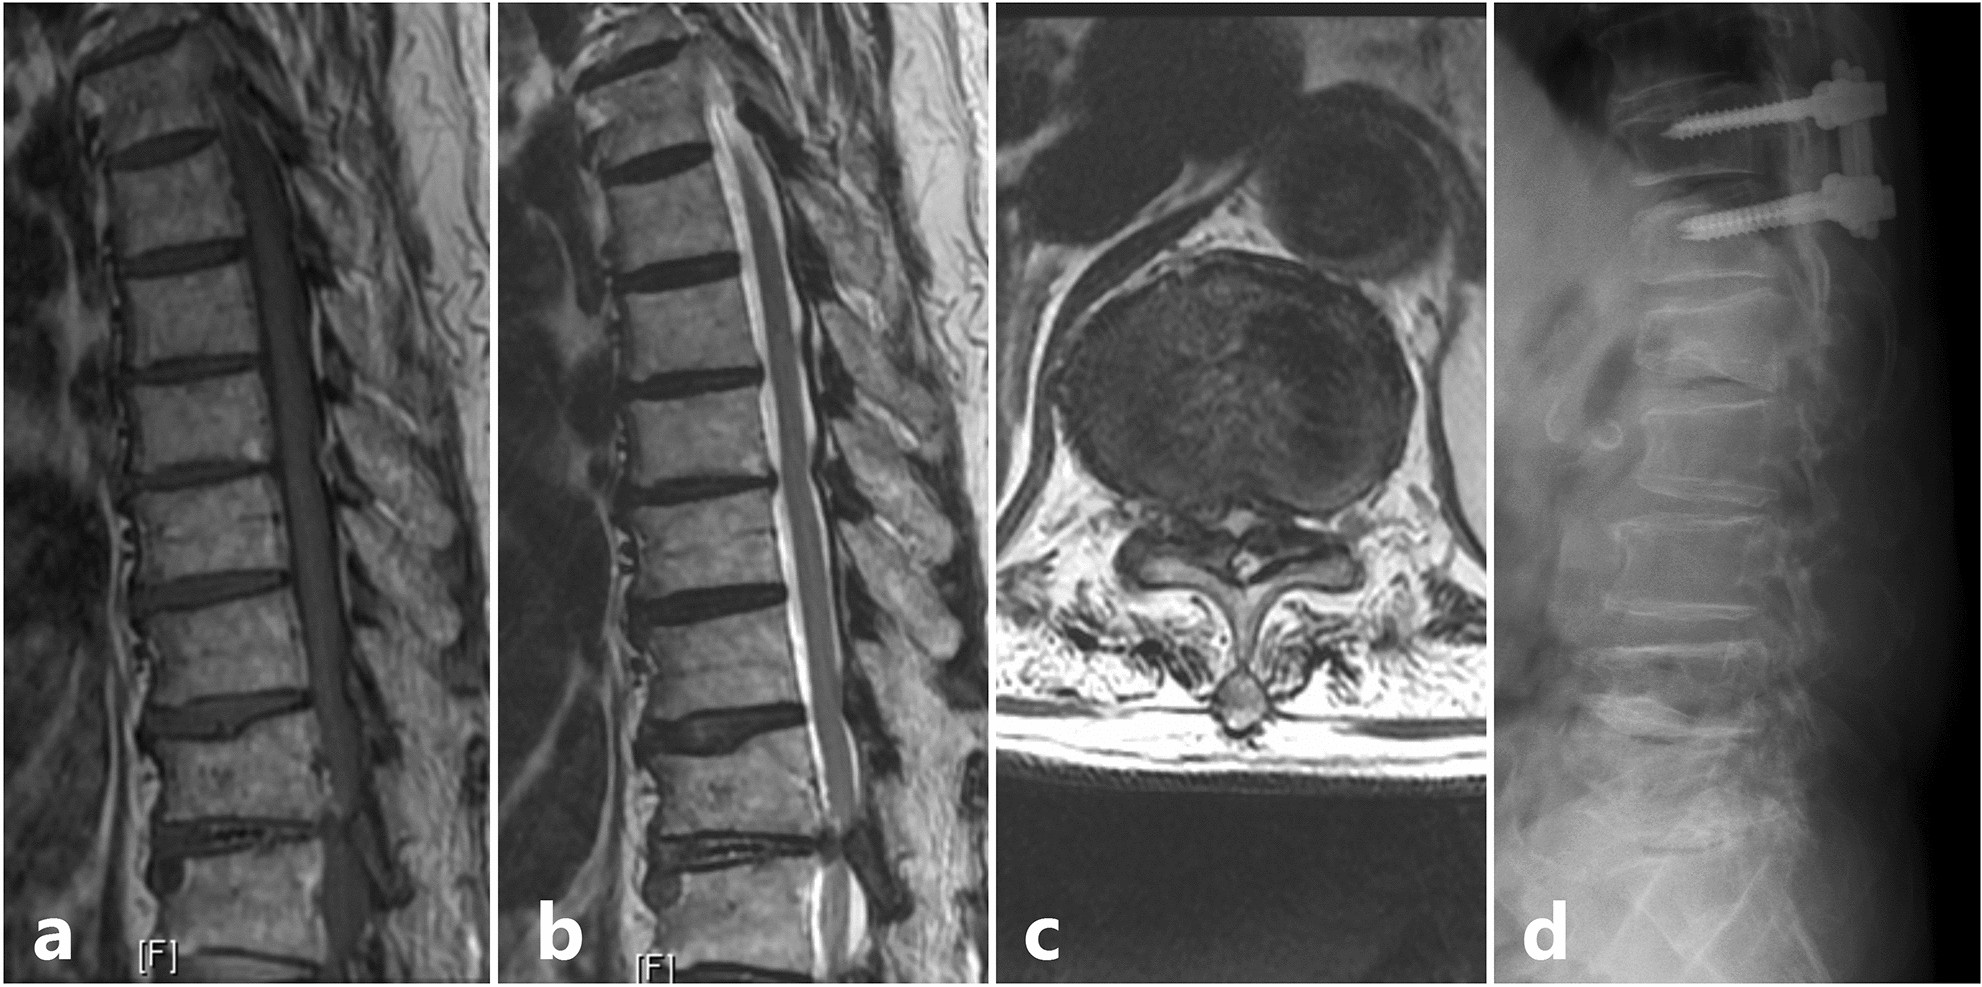

Figure 3

Scenario of a patient with solitary thoracic lesion who presented with category 2 signs; (a) Sagittal T1 weighted MRI showing an Ossified Ligamentum Flavum (OLF) at T11-T12 level; (b) Sagittal T2 weighted MRI; (c) Axial T2 weighted MRI showing the significant stenosis caused due to the OLF at T11-T12 level; (d) Post decompression and stabilization lateral view X-ray image.